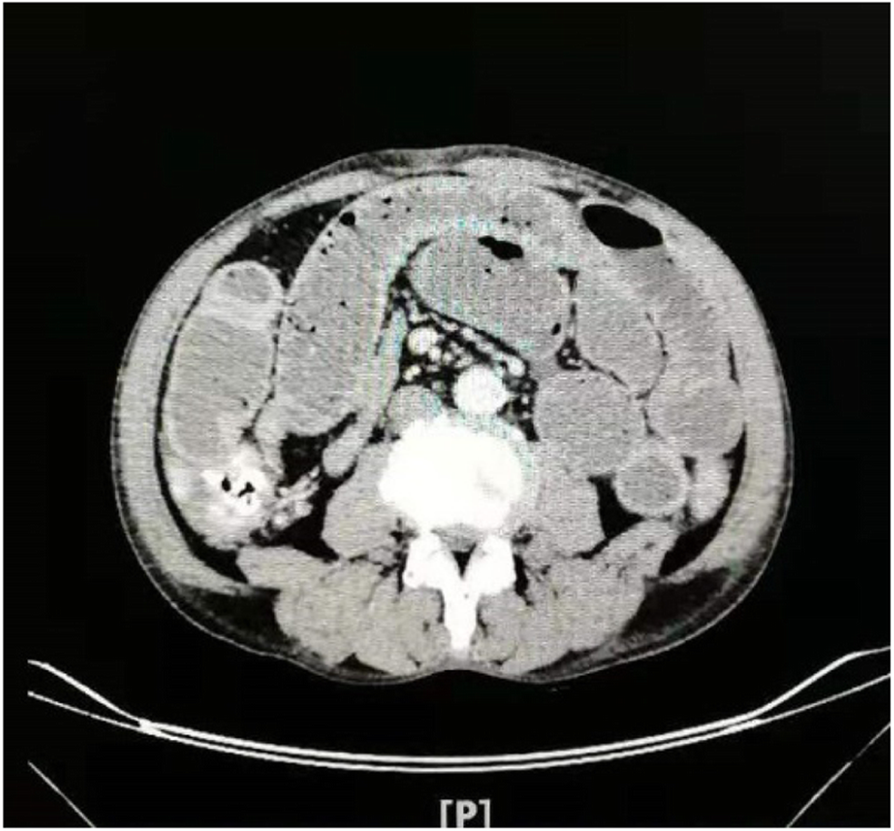

Fig. 1From: A case report of intestinal obstruction caused by cryptogenic multifocal ulcerous stenosing enteritisPreoperative abdominal CT examination showed small bowel obstructionBack to article page